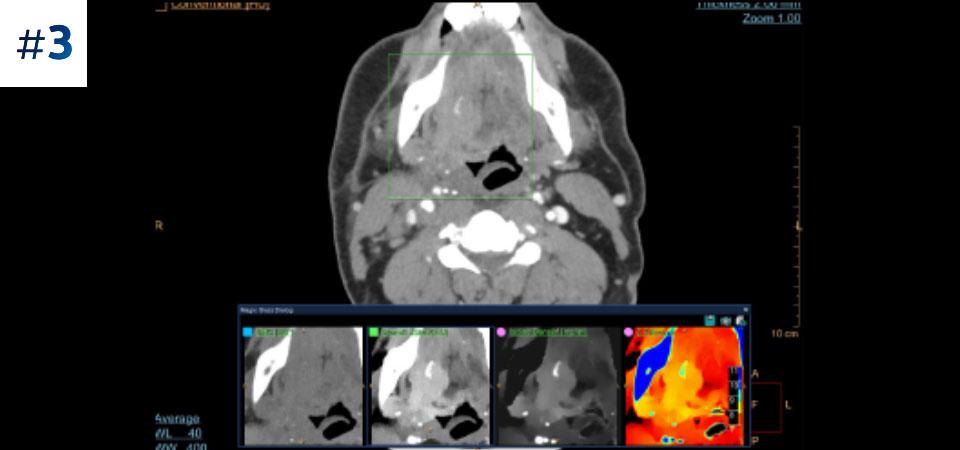

Neck mass

Our Philips spectral-detector CT allows us to acquire conventional and spectral data in one scan, with no change in our current workflow.